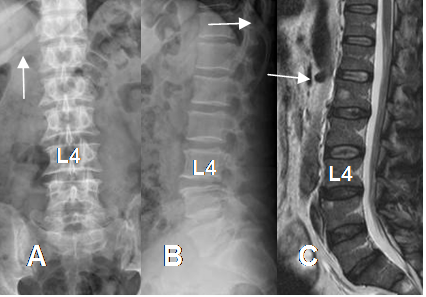

Fig 28. Anormalidad en la segmentación lumbosacra en Rx AP.

A: Presencia de solo 4 segmentos lumbares.

B: 5 segmentos lumbares, con articulación bilateral entre S1 y S2.

C: Hemisacralización izquierda de L5.

Fig 29. Anormalidad en la segmentación lumbosacra en Rx AP.

A: Articulación bilateral entre S1 y S2 y B: Hemisacralización izquierda de L5.